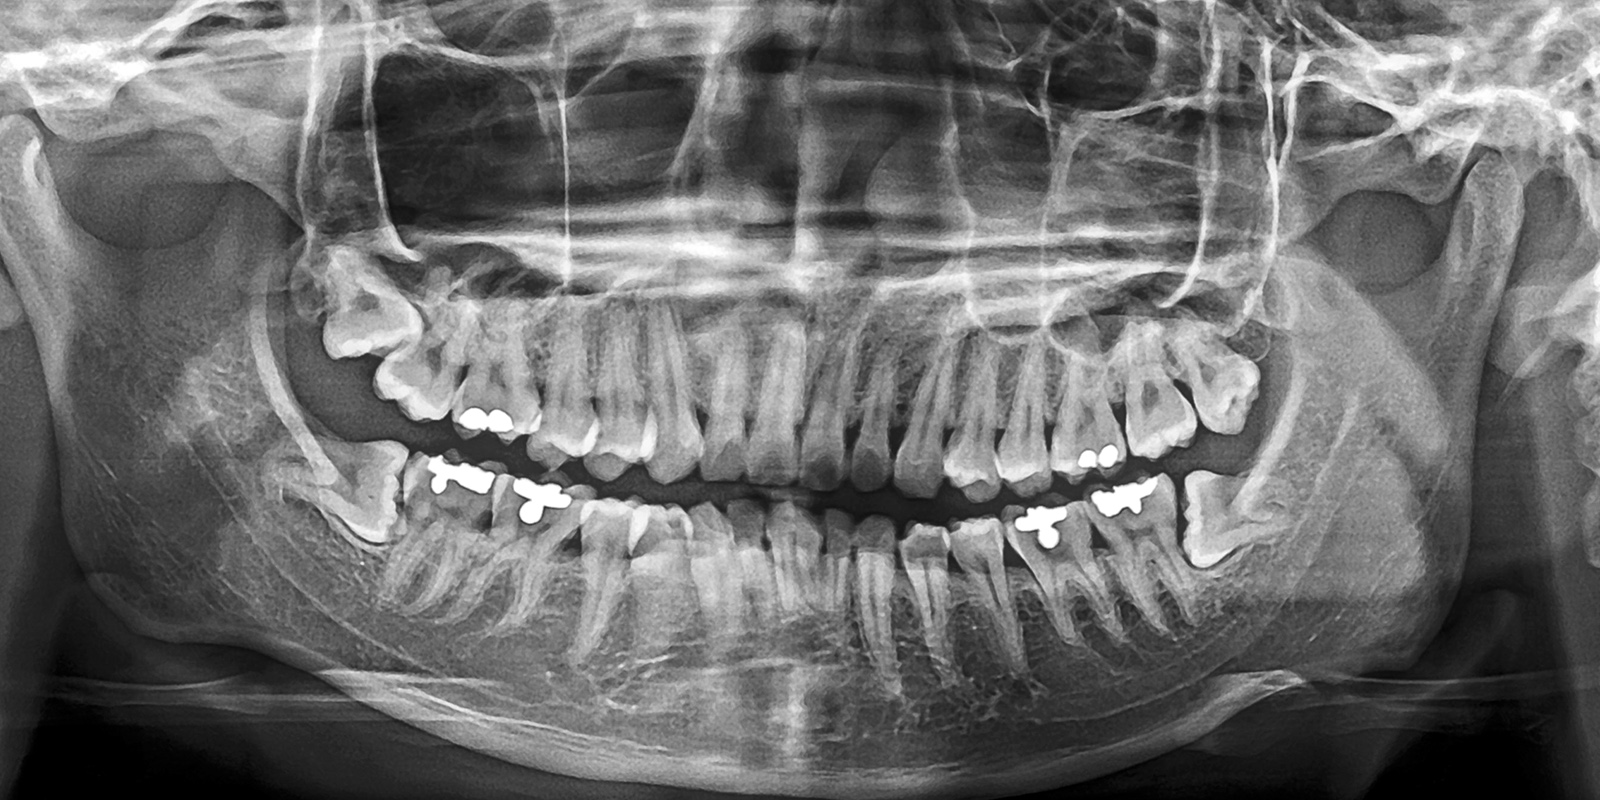

「パノラマレントゲン」の活用

パノラマレントゲンは、お口全体を1枚の画像で撮影できる広範囲のレントゲン写真です。これにより、親知らずの位置や向き、そして周囲の歯との関係がひと目でわかります。

特に下あごの親知らずは、大事な神経である下歯槽神経の近くにあることが多いです。そのため、抜歯による神経損傷のリスク評価が非常に重要となります。

パノラマ撮影を用いることで、神経との距離や重なり具合を事前に確認することができます。これにより、安全で的確な治療計画を立てる手助けとなります。